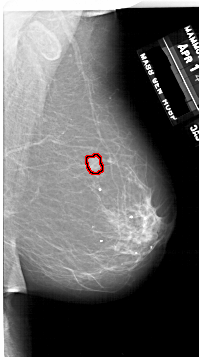

A_1747_1.RIGHT_MLO

RIGHT_MLO LINES 6421 PIXELS_PER_LINE 3571 BITS_PER_PIXEL 12 RESOLUTION 43.5 OVERLAY

FILE: A_1747_1.RIGHT_MLO.OVERLAY

TOTAL_ABNORMALITIES 1

ABNORMALITY 1

LESION_TYPE MASS SHAPE LOBULATED MARGINS ILL_DEFINED

ASSESSMENT 4

SUBTLETY 3

PATHOLOGY BENIGN

TOTAL_OUTLINES 1

BOUNDARY